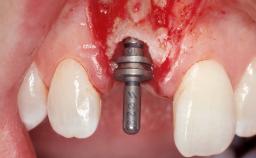

Late Placement of an Implant in a Maxillary Left Central Incisor Site

A 36-year-old female patient was referred for the replacement of the upper left central incisor (tooth 21), which had fractured. Although the tooth had been asymptomatic for many years, the crown began to loosen, at which time she presented to her dentist for an assessment. Teeth 21 and 22 had both been endodontically treated many years previously. She was a healthy individual and a non-smoker.

Bone Augmentation Horizontal|Staged

Augmentation Materials Xenogenous|Membrane

Placement Protocol Early or late implant placement